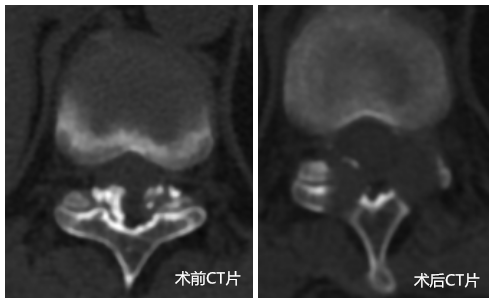

陈远明主任再次通过细致的查体、询问病史,全面的评估病情后提出症状与腰椎病变的影像学表现不吻合,“真凶”可能“另有其人”。经完善胸椎相关检查后,终于发现原来罪魁祸首是胸椎胸11/12黄韧带肥厚、钙化,压迫硬膜囊造成的胸椎管狭窄症。

胸椎管狭窄症常规的治疗方法是内固定下椎管减压,切除后方的椎板。此为开放手术,创伤大,而张阿姨更倾向于微创手术。如何既做到微创,又保证疗效,这让大家犯了难。在张阿姨的支持与信任下,经过反复的科室大讨论,陈主任决定行广西首例、全国也仅有极少量报道的胸椎椎间孔镜术。

经过严谨的术前评估,张阿姨被送入手术室,在我院脊柱微创专家、脊柱一区主任陈远明博士及周先明副主任的主持下,历时近2个小时,手术圆满成功。术后陈主任笑言:术前整晚失眠,脑海中一直在演练手术的穿刺入路及操作的注意事项,是患者的支持与信任给了我们动力。